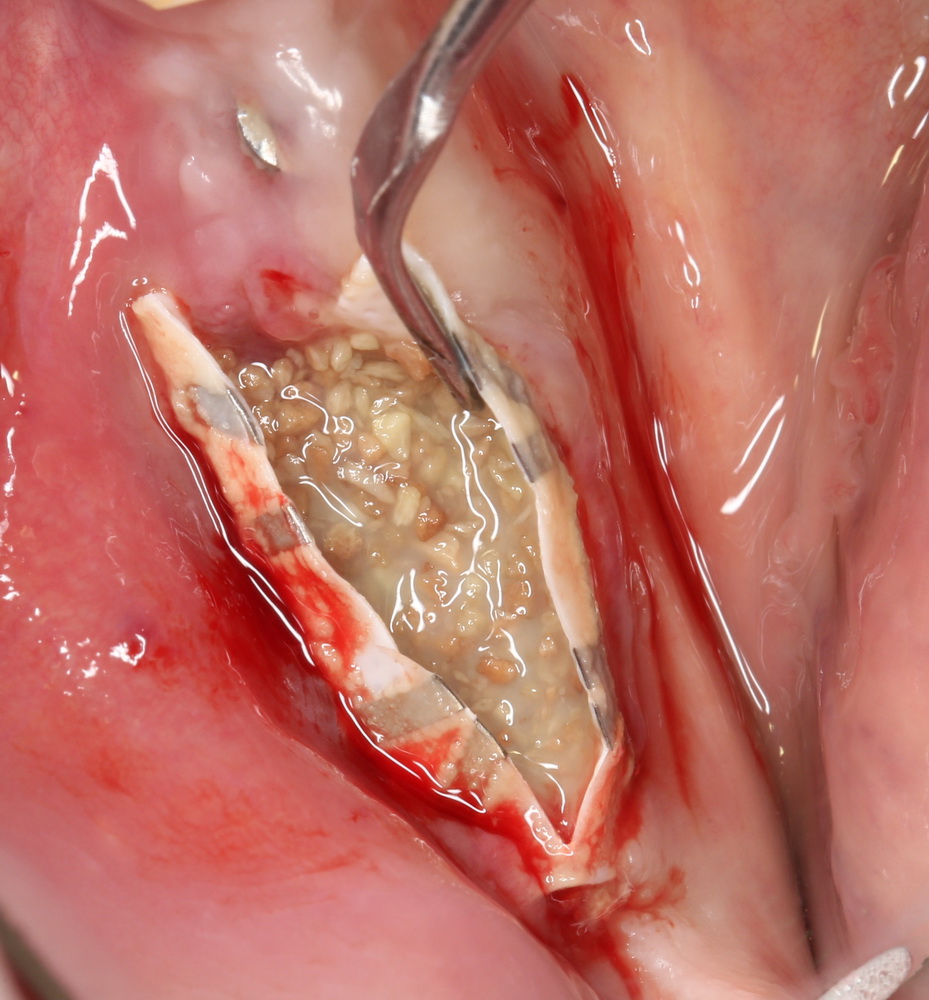

В этом случае остеопластика делается отдельной процедурой. Ее принципы точно те же, но уже без импланта. Например:

Имплантировать в таких условиях — заведомо обрекать себя на хреновый, с точки зрения эстетики и функциональности, результат. Поэтому первым этапом проводим остеопластику. Объем небольшой, использовать в таких объемах костный блок не очень рационально. Воспользуемся аутокостной стружкой и мембраной.

Сначала фиксируется BioGide. Это легко:

Затем укладывается и конфигурируется аутокостная стружка:

Если после этого BioGide намочить физраствором, им легко укрыть получившийся объем: